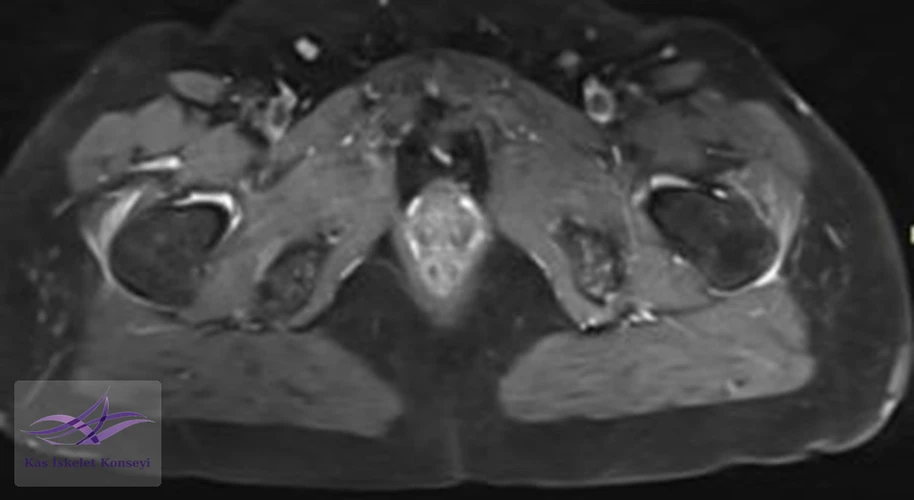

İncelemeler: Lomber MRG: L4-5 diskal bulging ve sol foraminal stenoz var. Kalça MRG istendi, iki yanlı trokanterik bursit rapor edildi.

Resim 5. Kalça MRG, aksiyal kesit.